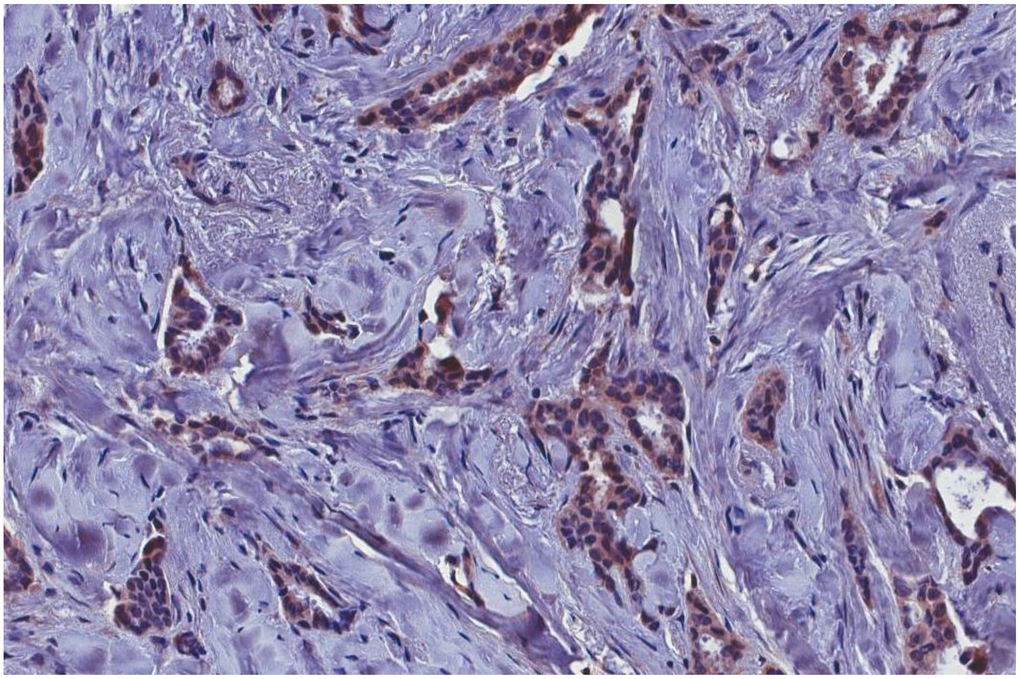

The immunohistochemical analysis showed the presence of p14 protein in all MMTVels positive tumors, whereas all negative MMTVels tumors were negative for p14 (Figures 2, 3).

Figure 2. MMTVels-positive infiltrating breast carcinoma cells positive for p-14 protein with immunohistochemical analysis. MMTVels: MMTV env-like sequence.

Figure 3. MMTVels negative infiltrating breast carcinoma cells negative for p-14 protein with immunohistochemical analysis (arrows: groups of cancer cells). MMTVels: MMTV env-like sequence.

P14, a multifunctional 98 amino acid peptide, is the signal peptide of the MMTV envelope precursor, localized in the nucleolus of cells harboring the virus with nucleo-cytoplasmic shuttling [10]. It is a tumor modulator phosphoprotein, endogenously phosphorylated by two serine kinases, CK2 at serine 65 and PKC at serine 18. P14 functions as an oncogene when serine 65 is phosphorylated, while it functions as an anti-oncogene when serine 18 is phosphorylated [10]. It is expressed on the surface of MMTV-associated murine and human cells [33]. P14 was immunohistochemically detected in all cases positive for MMTVels, whereas was absent in all negative cases. This result strengthens the molecular data.

Immunohistochemical assay was performed on 5 μm-thick paraffin sections. The antigen retrieval was achieved with MS-unmasker solution (DIAPATH, Martinengo, BG, Italy) in a microwave. Histostain–Plus kit (Invitrogen, Carlsbad, CA, USA) was used according to the manufacturer’s protocol. The slides were incubated with a primary antibody, rabbit polyclonal anti-MMTV-p14 (1:500 dilution), and then developed with diaminobenzidine chromogen (DAKO, Glostrup, Denmark) and counterstained with hematoxylin. Negative control included the omission of the primary antibody.